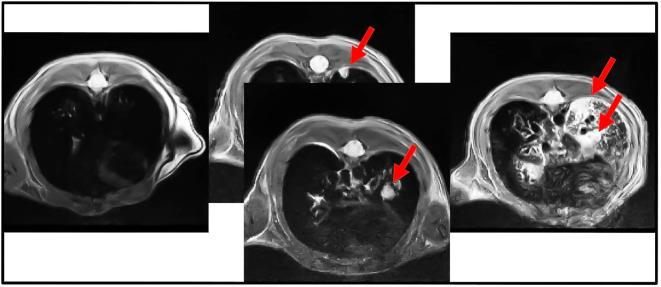

KRAS and KRAS-LKB1 conditional transgenic animal models were bred and genotyped. The tumors were inducted using adeno-CRE-recombinase system. The mice were housed in a Digital Ventilated Cage (DVC) rack measuring the locomotor activity continuously for 24/7. The progression of the tumors was monitored with MRI. The DVC system evaluated a reduction in animal locomotion during the tumor progression.

培育KRAS和KRAS-LKB1条件性转基因动物模型并进行基因分型。使用腺病毒-CRE重组酶系统诱导肿瘤。将小鼠饲养在数字通风笼(DVC)架中,每周7天、每天24小时连续测量其运动活动。用MRI监测肿瘤进展。DVC系统评估肿瘤进展过程中动物运动的减少情况。